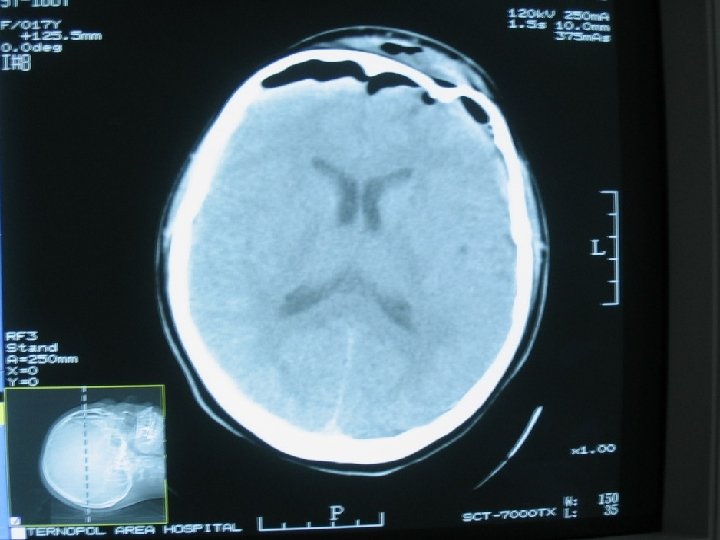

l Сдавление головного мозга: l У 2 – 10% пстрадалых из ЧМТ l Характеризируется жизненно опасным наростанием общемозговых, очагових и стволовых симптомов. Причины: Епидуральние гематомы; Субдуральные гематомы; Внутримозговые гематомы; Вдвленные переломы костей черепа; Очаг розмозжения с перифокальным отеком; Субдуральные гигромы; Пневмоцефалия. l l l l

l. Характерные признаки: l симптомы дислокации : l ухудшение росстройств сознания, очаговой (с – м Вебера) и общемозговой симптоматики; l светлый промежуток; l епиприпадки; l симптом Кушинга (АТ, брадикардия)

l. Диагностика: l. Оцнка неврологического статуса; l. Краниография; l. Ехо. Ес; l. АКТ; l. При отсутствии АКТ – поисковые фрезевые отверстия

l Лечение: Краниотомия (краниектомия) l Удаление гематомы (в первые 3 часа с момента госпитализации) l Коррекция внутричерепного давления l l Консервативное лечение гематом: Дислокация срединних структур не более 5 мм 2. Отсутствие контрлатеральной вентрикуломегалии 3. Отсутствие компресии базальных цыстерн 4. Уровень сознания 13 -15 б по ШКГ. 1.